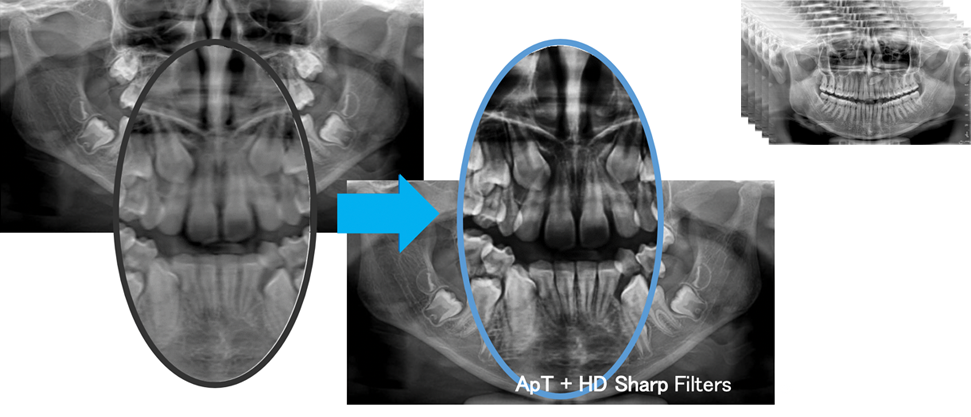

MultiPANで撮影された5層の画像からクリアな画像を自動選択。

常に診断に適した画像を提供します。

多数の画像フィルターから症例に適したフィルターをお選びいただけます。